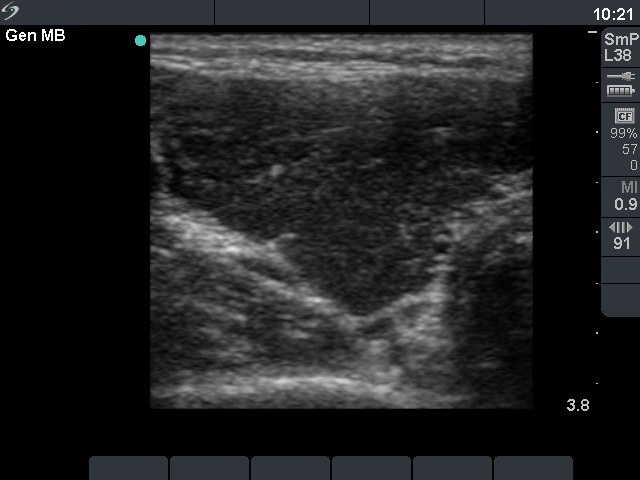

First investigation 6 months after delivery (first and second rows of images)

Clinical presentation: a 22-year-old woman was referred for an evaluation of a newly discovered hypothyroidism. She had fatigue and hair loss. She has been delivered 6 months before present investigation.

Palpation: the thyroids were enlarged and firm.

Functional state: hypothyroidism with TSH 47.7 mIU/L.

Ultrasonography: the thyroids were hypoechogenic without any nodule. The vascularization was increased.Cytology resulted in Hashimoto's thyroiditis.

Clinical diagnosis: hypothyroidism, post partum thyroiditis.